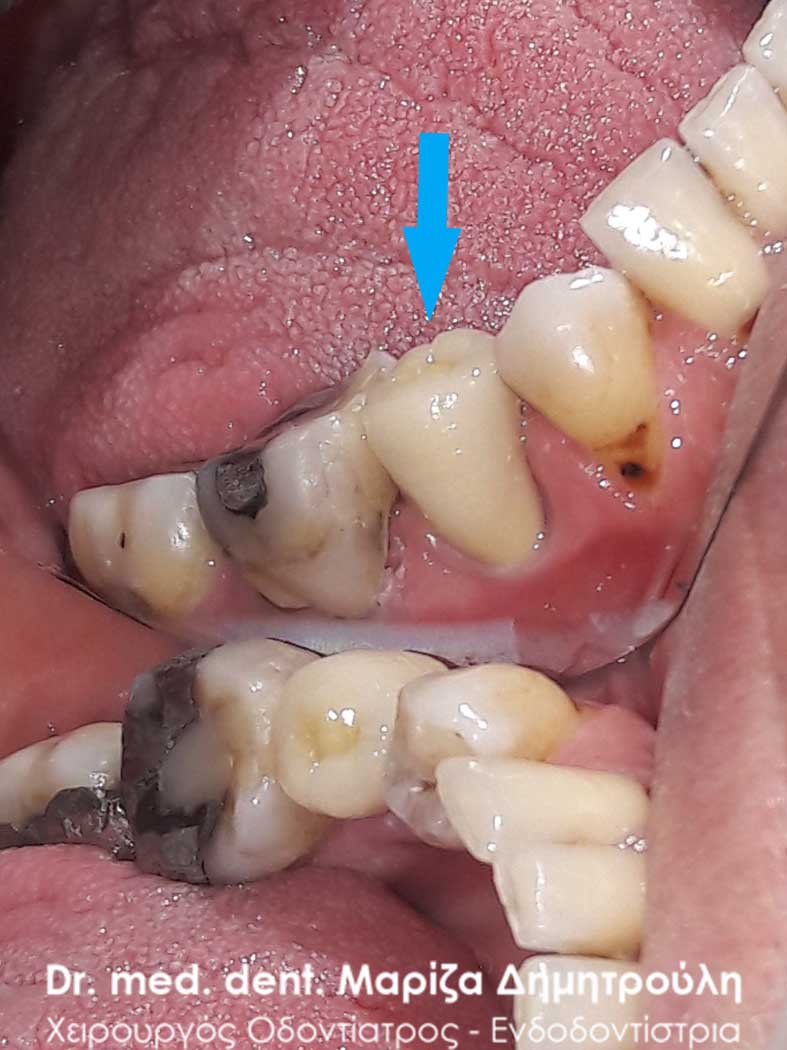

Αρχική κλινική εικόνα του μεγάλου οδοντικού ελλείμματος